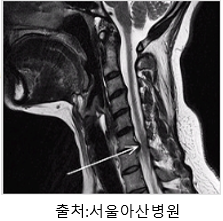

3. 영상 검사: 목 디스크를 확인하기 위해 X-ray, MRI (자기공명영상), CT (컴퓨터 단층 촬영) 등의 영상 검사가 수행될 수 있습니다. 이를 통해 디스크의 위치, 크기, 손상 정도 등을 평가할 수 있습니다.